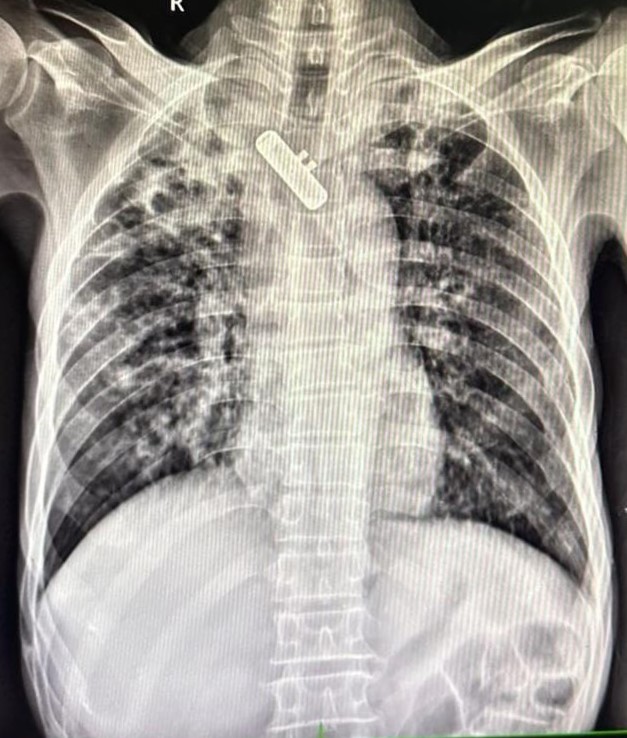

| 149 | IGGMC, Nagpur, Nagpur | P2 | 29-4323 | Samina Parveen | Consent taken on Paper | 30 Yrs. |

Provisional Diag : Bilateral Tubercular Pleural Effusion

Final Diag : Bilateral Tubercular Pleural Effusion With Right Sided Pigtail Infiltration |

TB Case (Confirmed) | Bilateral CP Angle Blunting With Bilateral Homogenous Opacity Left Zone With Pigtail Right Pleural Effusion | Abnormality visible on x-ray |